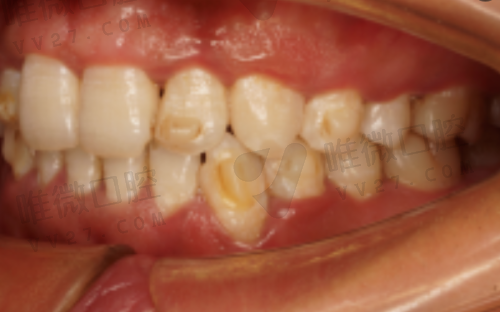

擅长项目: 烤瓷牙、活动义齿、牙列不齐矫正、根管治疗

医院优势: 岳氏口腔是伊春本地“老品牌”口碑诊所之一,多年来服务于本地居民,技术稳定,医生流动性小,因此老顾客和家庭患者占比较高。该诊所特色在于传统治疗手法的沉淀与稳定性,对于年纪较大的患者更有亲和力。另外,其义齿修复口碑不错,有患者反馈佩戴多年仍无明显问题。